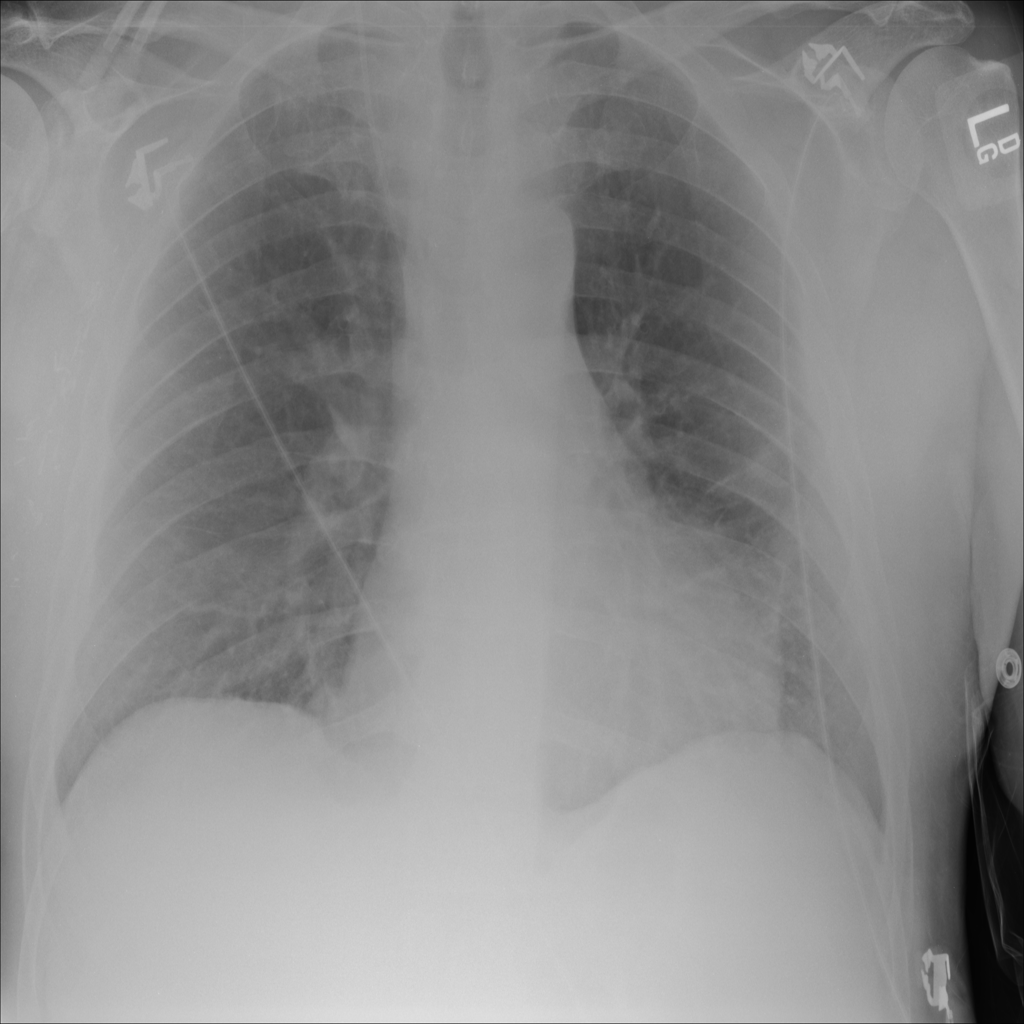

PAT-24D9 · IMG-006Edema

PAT-24D9 · IMG-006

AP